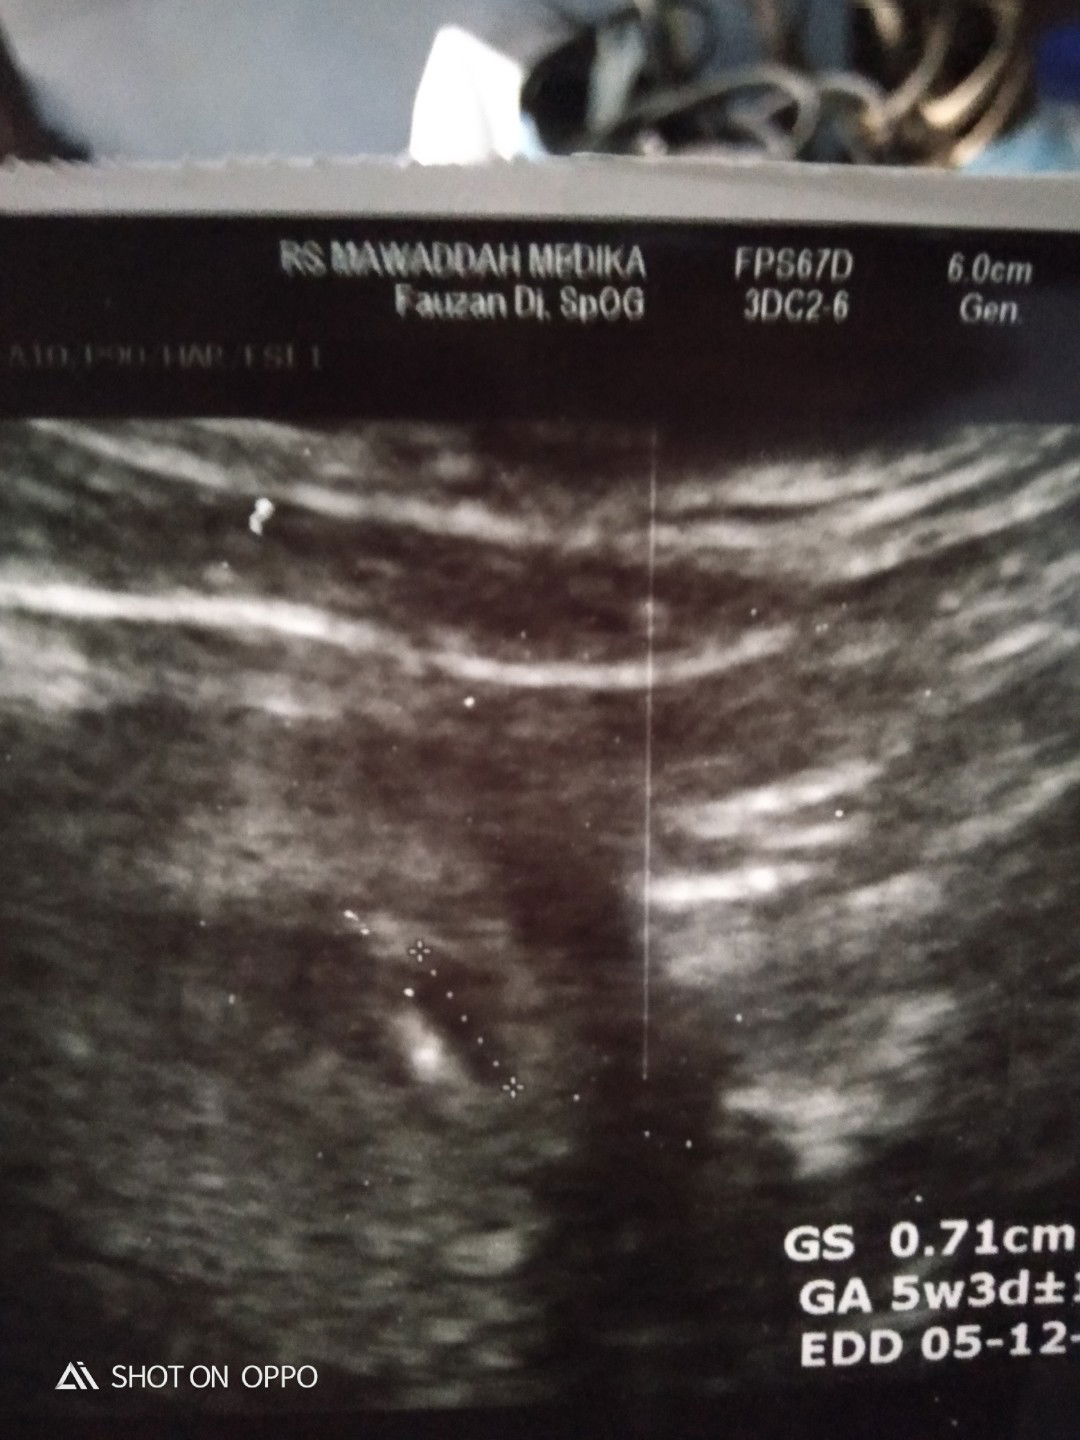

assalamualaikum bunda", sedikit cerita y bun kemarin lusa saya periksa dan usg trus kata dokter usia sudah 5 minggu tp knp kok kecil sekali dan msih berupa kantung ya bun, apakah ini wajar? saya sempat khawatir sih bun,tolong tanggapannya y bun, terima kasih .